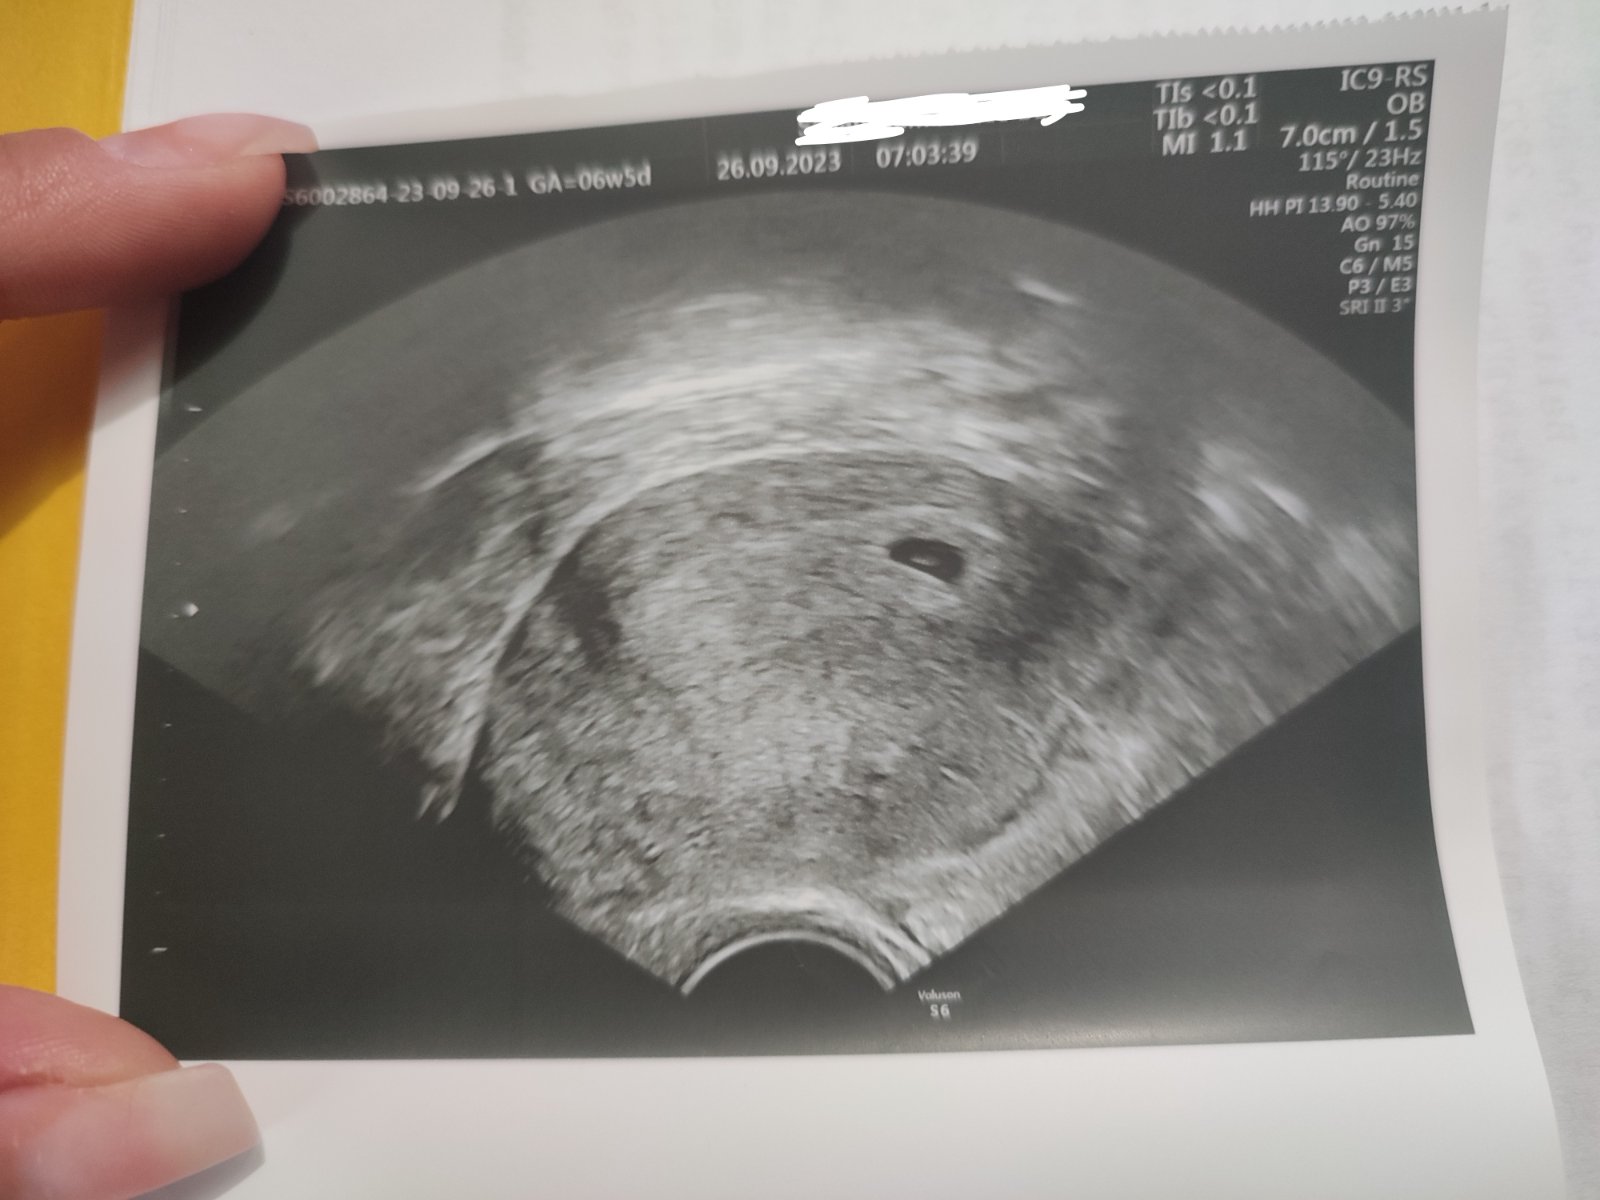

Posledná menštruácia bola 10.8.2023 a podľa toho by som mala byť 6+5 tt.

Dnes som bola na kontrole a povedala mi doktorka, že som mala zrejme posunutú ovuláciu, že nesedí týždeň podla sona. V ktorom týždni teda reálne by som mohla byť? hCG minulý utorok 19.9. 2023 bolo 281. Dnes mi už kontrolu hCG nerobili.

@anjelicek26 nepovedala mi práveže, preto sa pýtam tu, lebo som sa pozabudla spýtať jej. Srdiečko ešte nebilo. Čiže dnes by som mohla byť 5+3 ano? Testovala som sa po meškaní menštruácie a 14.9.2023 mi Digi test ukázal 1-2.

Lekarka ti nepovedala, ze o kolko? Vidno zarodok embrya, srdiecko este nebilo? Preto asi hovori, ze posunuta ovu... urcite do buducej kontroly nabehne... ked si 19.9. mala hcg len 281 to si tabulkovo bola ovulka+17 teda 4+3 a dnes 5+3 a to ti s fotkou sedi ako ma... kedy si mala prvy pozzitivny test?